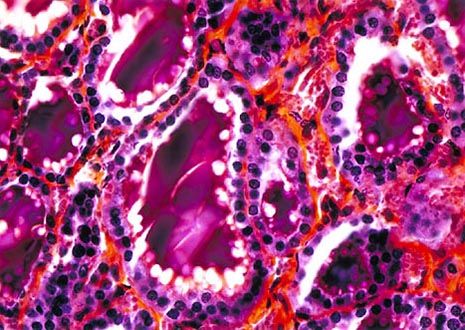

Thyroid Gland

Located in the throat just below the Adam’s apple is the small, lobed gland known as the thyroid. The hormones secreted by the thyroid are active in a variety of bodily functions, but are most important to metabolism regulation.